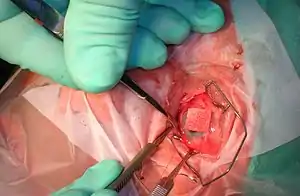

Ophthalmic surgery

Eye surgery, also known as ocular surgery, is surgery performed on the eye or its adnexa by an ophthalmologist. The eye is a fragile organ, and requires extreme care before, during, and after a surgical procedure. An eye surgeon is responsible for selecting the appropriate surgical procedure for the patient and for taking the necessary safety precautions.